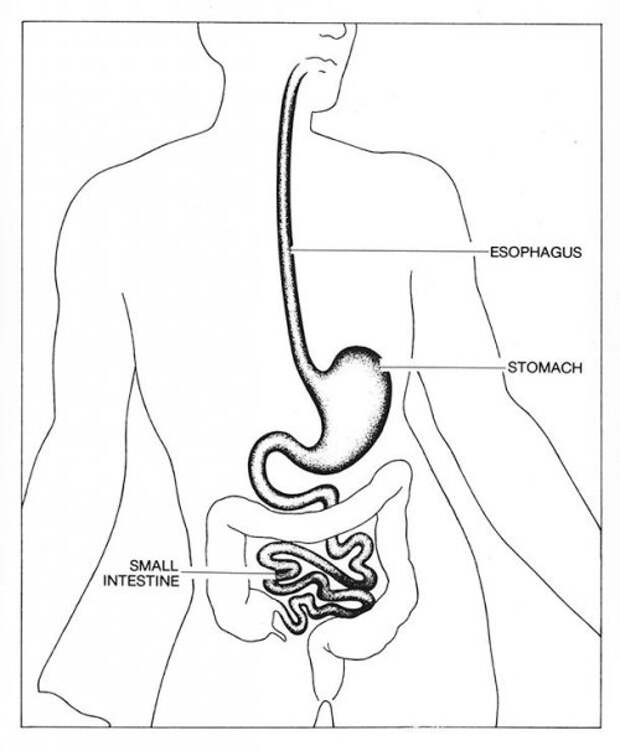

25. На путешествие по пищеводу у еды уходит всего 7 секунд

Фото: Wikipedia Commons.com

10. Пищевод перенаправляет пищу из ротовой полости в желудок, и в этой миссии ему помогают специальные мышцы. Процесс «доставки» называется перистальтикой глотания.

Фото: Database Center for Life Science (DBCLS)

25. На путешествие по пищеводу у еды уходит всего 7 секунд

Фото: Wikipedia Commons.com

10. Пищевод перенаправляет пищу из ротовой полости в желудок, и в этой миссии ему помогают специальные мышцы. Процесс «доставки» называется перистальтикой глотания.

Фото: Database Center for Life Science (DBCLS)